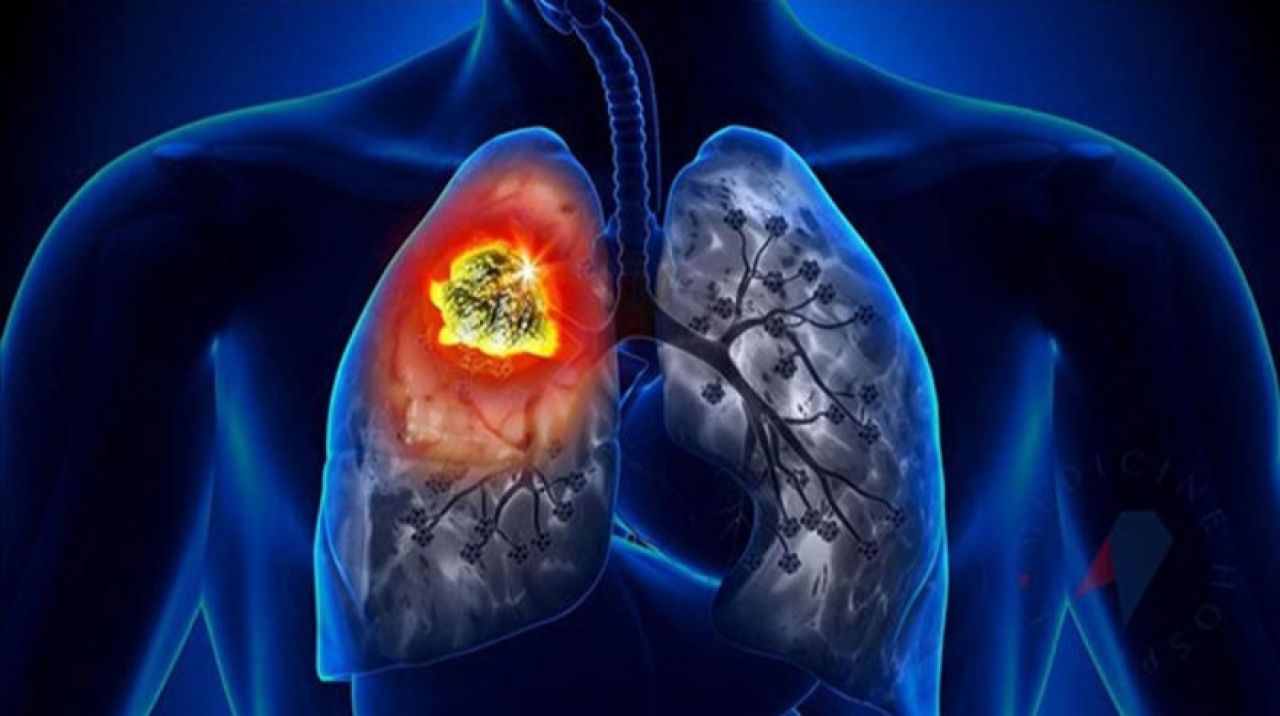

Ankara Ülkemizde de akciğer kanseri oldukça yaygın görülüyor. 2020 yılında 40 binin üzerinde yeni akciğer tanısı konulduğu belirtiliyor. Akciğer kanseri, genellikle erken dönemlerinde fazla belirti vermemesi veya en tipik belirtisi olan öksürük geliştiğinde sigara içen kişilerin ‘sigara öksürtüyor’ düşüncesiyle hekime geç başvurmaları nedeniyle sıklıkla ileri evrede teşhis ediliyor. Tedavinin gecikmesi de hastanın hayatını kaybetmesine yol açıyor. Acıbadem Ataşehir Hastanesi Göğüs Cerrahisi Uzmanı Prof. Dr. Erdal Okur, oysa gerek cerrahi tedavide gerekse diğer tedavi yöntemlerinde yaşanan önemli gelişmeler sayesinde özellikle erken tanı konabilen ve cerrahi olarak tedavi edilebilen akciğer kanserinden tamamen kurtulmanın mümkün olabileceğini belirterek, “Hastalığın erken döneminde tanı konabilmesi için yüksek riskli olarak belirlenmiş, yoğun sigara içen veya geçmişte içmiş olan 50 yaş üzeri kişilere her yıl düşük radyasyon dozlu bilgisayarlı akciğer tomografi çekimi yapılması öneriliyor. Bu sayede henüz hiçbir belirti vermemiş erken evre akciğer kanserinin yakalanması mümkün olabiliyor” diyor. Peki hangi belirtiler akciğer kanserine işaret ediyor, ne zaman hekime başvurmak gerekiyor? Göğüs Cerrahisi Uzmanı Prof. Dr. Erdal Okur, “1-30 Kasım Dünya Akciğer Kanseri Farkındalık Ayı” kapsamında akciğer kanserinin belirtilerini anlattı; önemli uyarılarda bulundu!